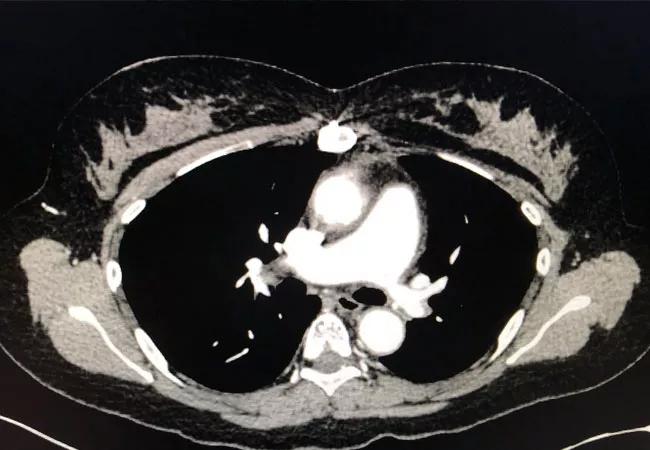

Above: Computed tomography angiography showing stenosis of the left pulmonary artery with vessel wall thickening.

The possibility that pulmonary artery involvement in TAK was the cause of this patient’s imaging findings was investigated. After receiving premedication prophylaxis, she safely underwent a CTA. This study was negative for pulmonary embolism and showed stenosis and wall thickening of the main left pulmonary artery with reduced blood flow corresponding to the abnormal perfusion scan. Using computerized visualization techniques, it was possible to determine that the pulmonary artery stenosis had been present at the time of the original diagnosis for which she had been treated.